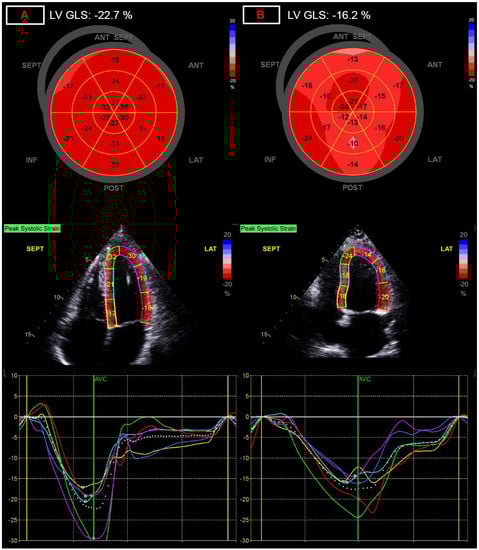

Dimensions of the right heart did not show statistical difference between the two groups. Among functional parameters, tricuspid annular plane systolic excursion values were significantly decreased in post-COVID patients (23.75 ± 2.8 vs. 22.5 ± 3.4 mm; p = 0.039), while tricuspid annular s’ velocity values were similar. However, right ventricular free wall strain values (−26.6 ± 3.80 vs. −23.8 ± 4.0%; p = 0.0003; Figure 3) were significantly decreased in post-COVID patients, showing the most significant change, and showing the largest relative difference between the two groups at 11.7% (Table 4).

Figure 3. Representation of alterations of right ventricular free wall strain (FWS) measurement. (A) panel: normal right ventricular free wall strain of −29.4%; (B) panel: decreased right ventricular free wall strain of −16.8%, after COVID-19 infection.